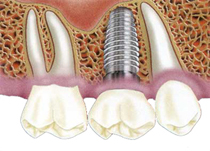

メインテナンス・定期健診

プロによる定期的なお口のメインテナンスを受けることで、歯やインプラントを長持ちさせることができます。

入れ歯が合わなくて痛い義歯 インプラントしたいインプラント

インプラントしたいインプラント 歯が変色しているホワイトニング